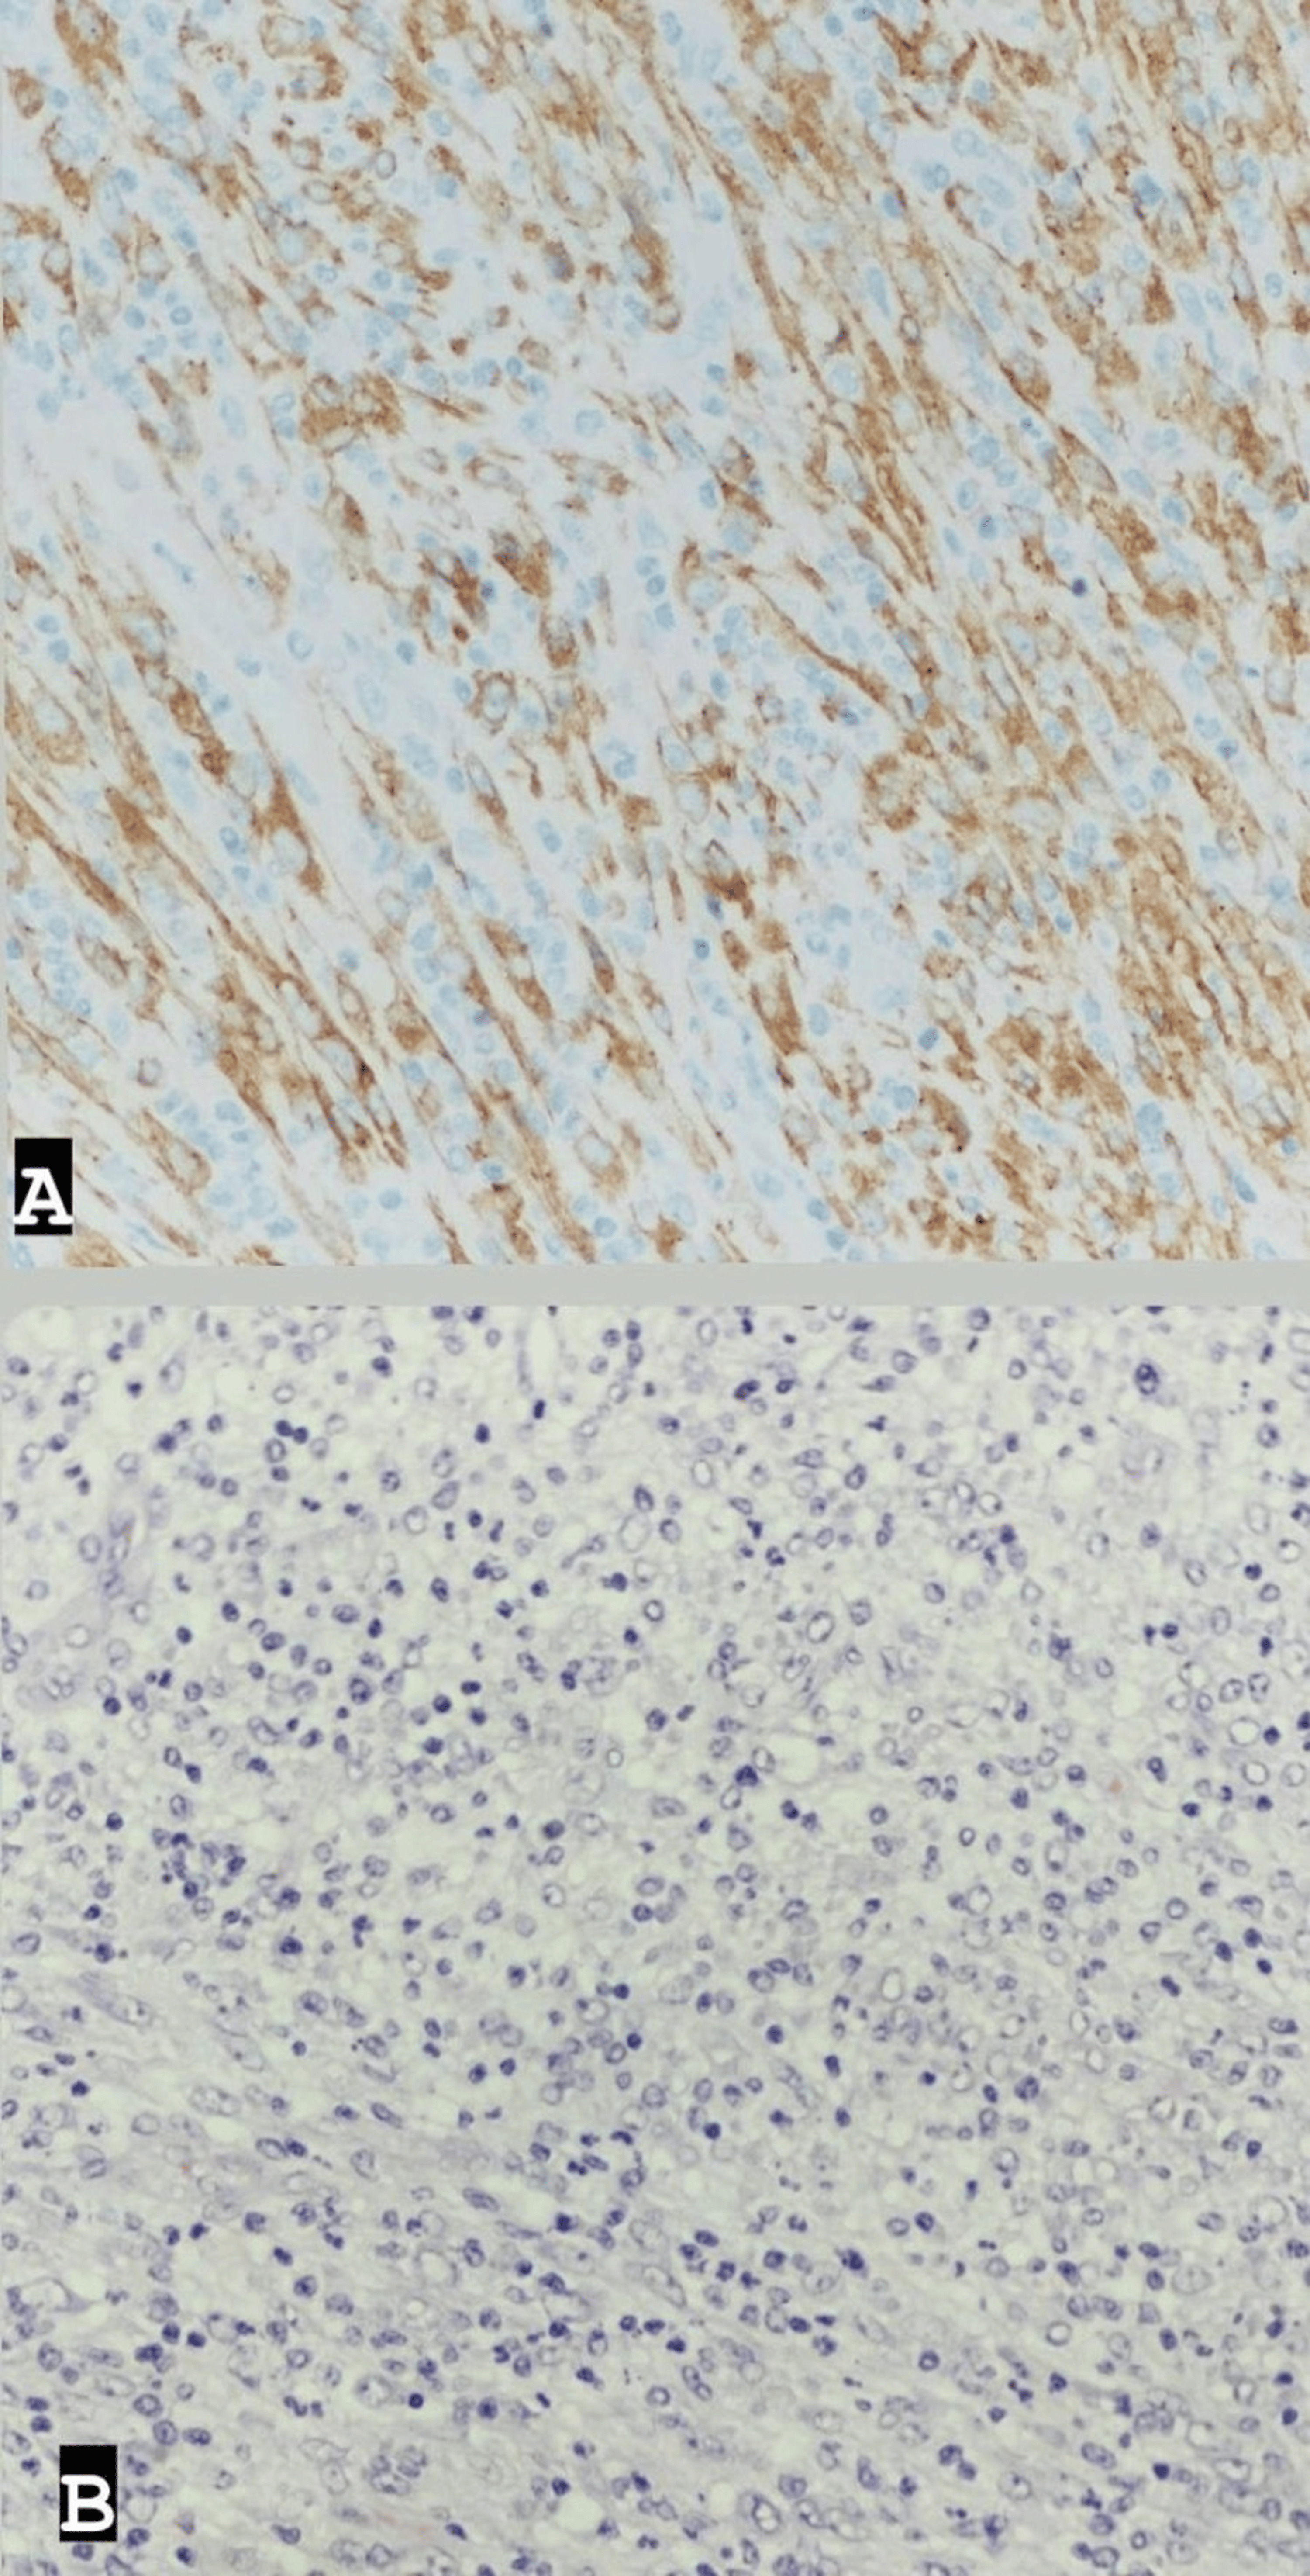

Post-surgery, the patient was admitted to the intensive care unit (ICU) for close monitoring before being transferred to the ward and discharged in stable clinical condition five days later. Histopathological examination of the excised mass revealed features consistent with an inflammatory myofibroblastic tumor, characterized by a well-demarcated cellular mass with a myxoid and highly vascularized background; spindled fibroblasts/myofibroblasts; and numerous lymphocytes, histiocytes, eosinophils, and plasma cells. Ganglion-like cells were also observed, with 5 mitotic figures per 10 high-power fields. No marked atypia or necrosis was noted. The tumor cells showed diffuse positivity for ALK (cytoplasmic), with rare cells positive for SMA (smooth muscle actin), and were negative for CD30, CD34, S100, Pan-CK, Myogenin, and CD117. CD68 highlighted histiocytes in the background, while CD45 highlighted inflammatory cells (Figure 3).

IMT is considered a distinct pathological entity. Both pulmonary and extrapulmonary IMTs are characterized by rearrangements involving the ALK (anaplastic lymphoma kinase) gene in up to 50% of cases, leading to activation of tyrosine kinase [2]. The typical immunohistochemical profile shows vimentin positivity, focal SMA positivity, and negativity for CD117 and CD34 [3,5]. These findings were consistent with the profile observed in our case, further supporting the diagnosis of IMT.